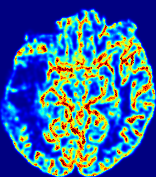

Slice #1Slice #2Slice #3Slice #4Slice #5Slice #6𝐕gt2subscriptnormsuperscript𝐕gt2\|{\bf{V}}^{\text{gt}}\|_{2}Refer to captionRefer to captionRefer to captionRefer to captionRefer to captionRefer to caption(a)Refer to captionRefer to captionRefer to captionRefer to captionRefer to captionRefer to caption(b)Refer to captionRefer to captionRefer to captionRefer to captionRefer to captionRefer to caption(c)Refer to captionRefer to captionRefer to captionRefer to captionRefer to captionRefer to caption(d)Refer to captionRefer to captionRefer to captionRefer to captionRefer to captionRefer to caption(e)Refer to captionRefer to captionRefer to captionRefer to captionRefer to captionRefer to caption(f)Refer to captionRefer to captionRefer to captionRefer to captionRefer to captionRefer to captionRefer to caption000.30.30.30.60.60.60.90.90.91.21.21.21.51.51.5(mm/s)𝑚𝑚𝑠(mm/s)

Figure 12: PIANO effectiveness and robustness testing: advection imaging via advection. Top row shows the ground truth 𝐕gt2subscriptnormsuperscript𝐕gt2\|{\bf{V}}^{\text{gt}}\|_{2} used for simulating pure advection. (a)-(f) refer to the results for 𝐕2subscriptnorm𝐕2\|{\bf{V}}\|_{2} estimated by PIANO, with simulated advection imaging series where Rician noise at levels 0%, 2%, 4%, 6%, 8%, 10% was added respectively.

Our goal here is to determine if PIANO can estimate a known velocity field from a concentration time-series consistent with this velocity field. To this end, for each patient in the ISLES 2017 training set, we treat the velocity field estimated by PIANO as the ground truth velocity field (𝐕gtsuperscript𝐕gt{\bf{V^{\text{gt}}}}), and the first image in the concentration time-series dataset {Cti}superscript𝐶subscript𝑡𝑖\{C^{t_{i}}\} (as described in Sec. 3) is used as the initial condition (C0superscript𝐶0C^{0}). We then simulate ‘advection imaging’ {Cti(Ω)|i=0, 1,, 40}conditional-setsuperscript𝐶subscript𝑡𝑖Ω𝑖0140\{C^{t_{i}}\in\mathbb{R}(\Omega)|i=0,\,1,\,\ldots,\,40\}, i.e., we create a time-series of concentration images driven by the velocity 𝐕:=𝐕gtassign𝐕superscript𝐕gt{\bf{V}}:={\bf{V^{\text{gt}}}} only via the advection PDE:

We further simulate noisy concentrations by adding Rician noise [24] with variances equalling 2%, 4%, 6%, 8%, 10% of the originally simulated concentrations {Cti}superscript𝐶subscript𝑡𝑖\{C^{t_{i}}\}. We then test how well PIANO can estimate the underlying velocity field via Eq. 15 with the same model settings (except without estimating the diffusion) as in Sec. 3 given the original and the noisy concentration time-series. Fig. 12 shows the estimated 𝐕est2subscriptnormsuperscript𝐕est2\|{\bf{V}}^{\text{est}}\|_{2} for one patient. Fig. 11 (a) shows the summarized estimation results for all 43 patients. PIANO almost perfectly captures the underlying velocity field, and maintains excellent performance even when estimating from concentrations with varying noise levels.